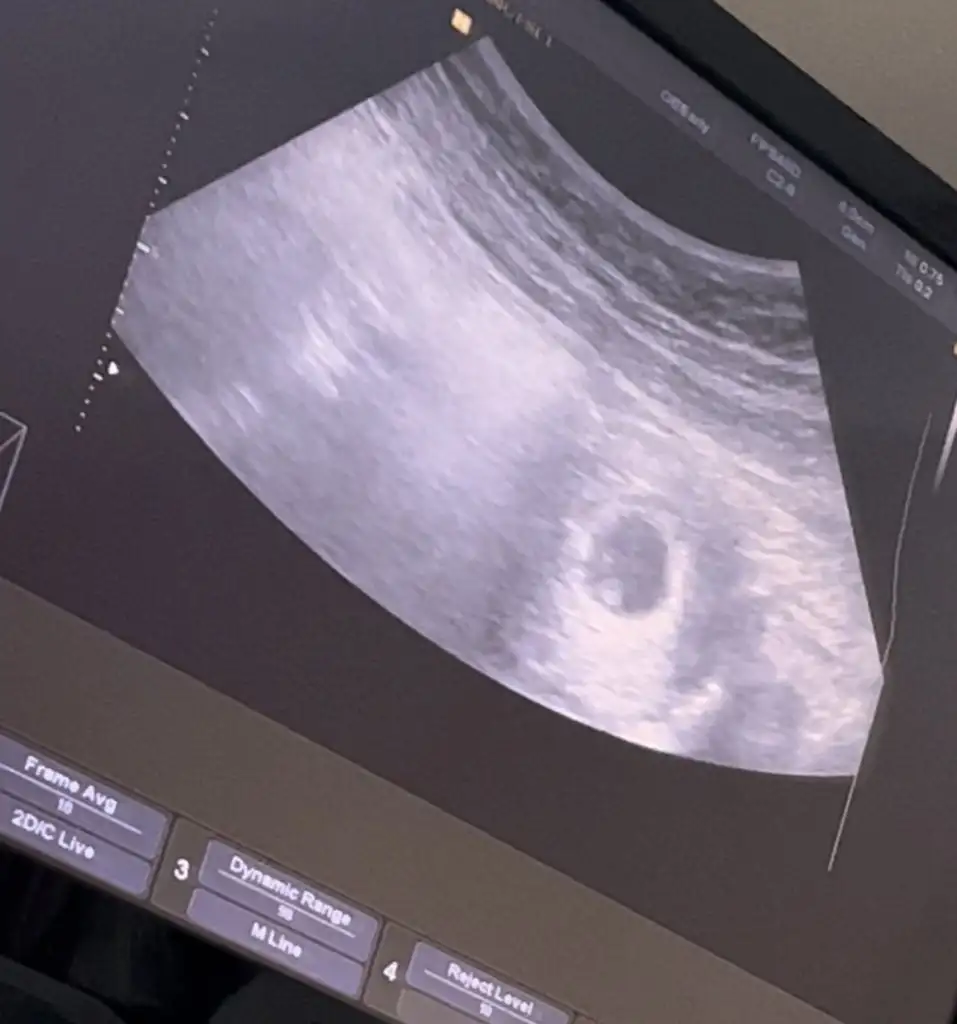

Tek yumurta ikizi mi canımYaaa çok teşekkür ederim bayadır tedavi sürecindeydim ister istemez tedirgin oldum ama çok teşekkür ederimilk önceliğim sağlıklı olması gebeliğin ikiz diyince bi şok geçirdim birde hiç bilgim olmadığı için benim de tek kese göründü ultrasan burdaki gibi ilk gebelik acemilik işte nası oluyo bilmediğim için dedim normal gebeliklerde de kese de böyle iki beyazlık mı görünüyor Eki Görüntüle 3197859 Eki Görüntüle 3197860

Tek kese göründü ama ikiz mi daha belli değil tek kalp atışı göründü ikizlerde kalp atışları sonra mı oluyo hiç bir bilgim de olmadığı içinTek yumurta ikizi mi canım

İkiz olabilir belkide silik çıkmamış gayet net :))

Koyuluk benim ilk transferimdede boyleymis gecen baktim arkadaslara atmisim kan degerim 1600 lerdeymis 12.gunde hatta doktorum kesin ikiz gibi konusmustu. Ama kese tek olustu, hayirlisi be canımm saglicakla gelsinler , senin nasil gidiyorKoyuluğu baya iyi gibi 5.güne göre galba ikizler geliyo canım maşallah